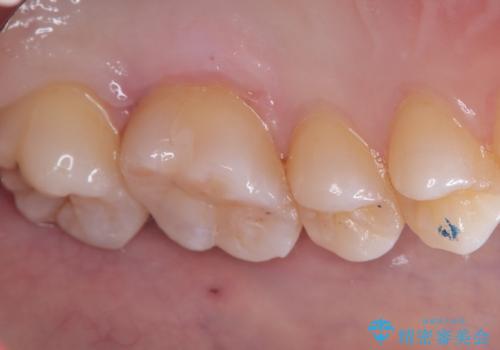

咬合面に穴が空き、歯の中でう蝕が広がっていました。この歯が過去に咬合面う蝕を経験しCR修復を受けていること、今回歯質とCRの境目からの二次う蝕になっていることを説明し、適合や材料安定性の良いセラミックインレーでのやり替えとなりました。

セット時はラバーダム防湿を行っています。